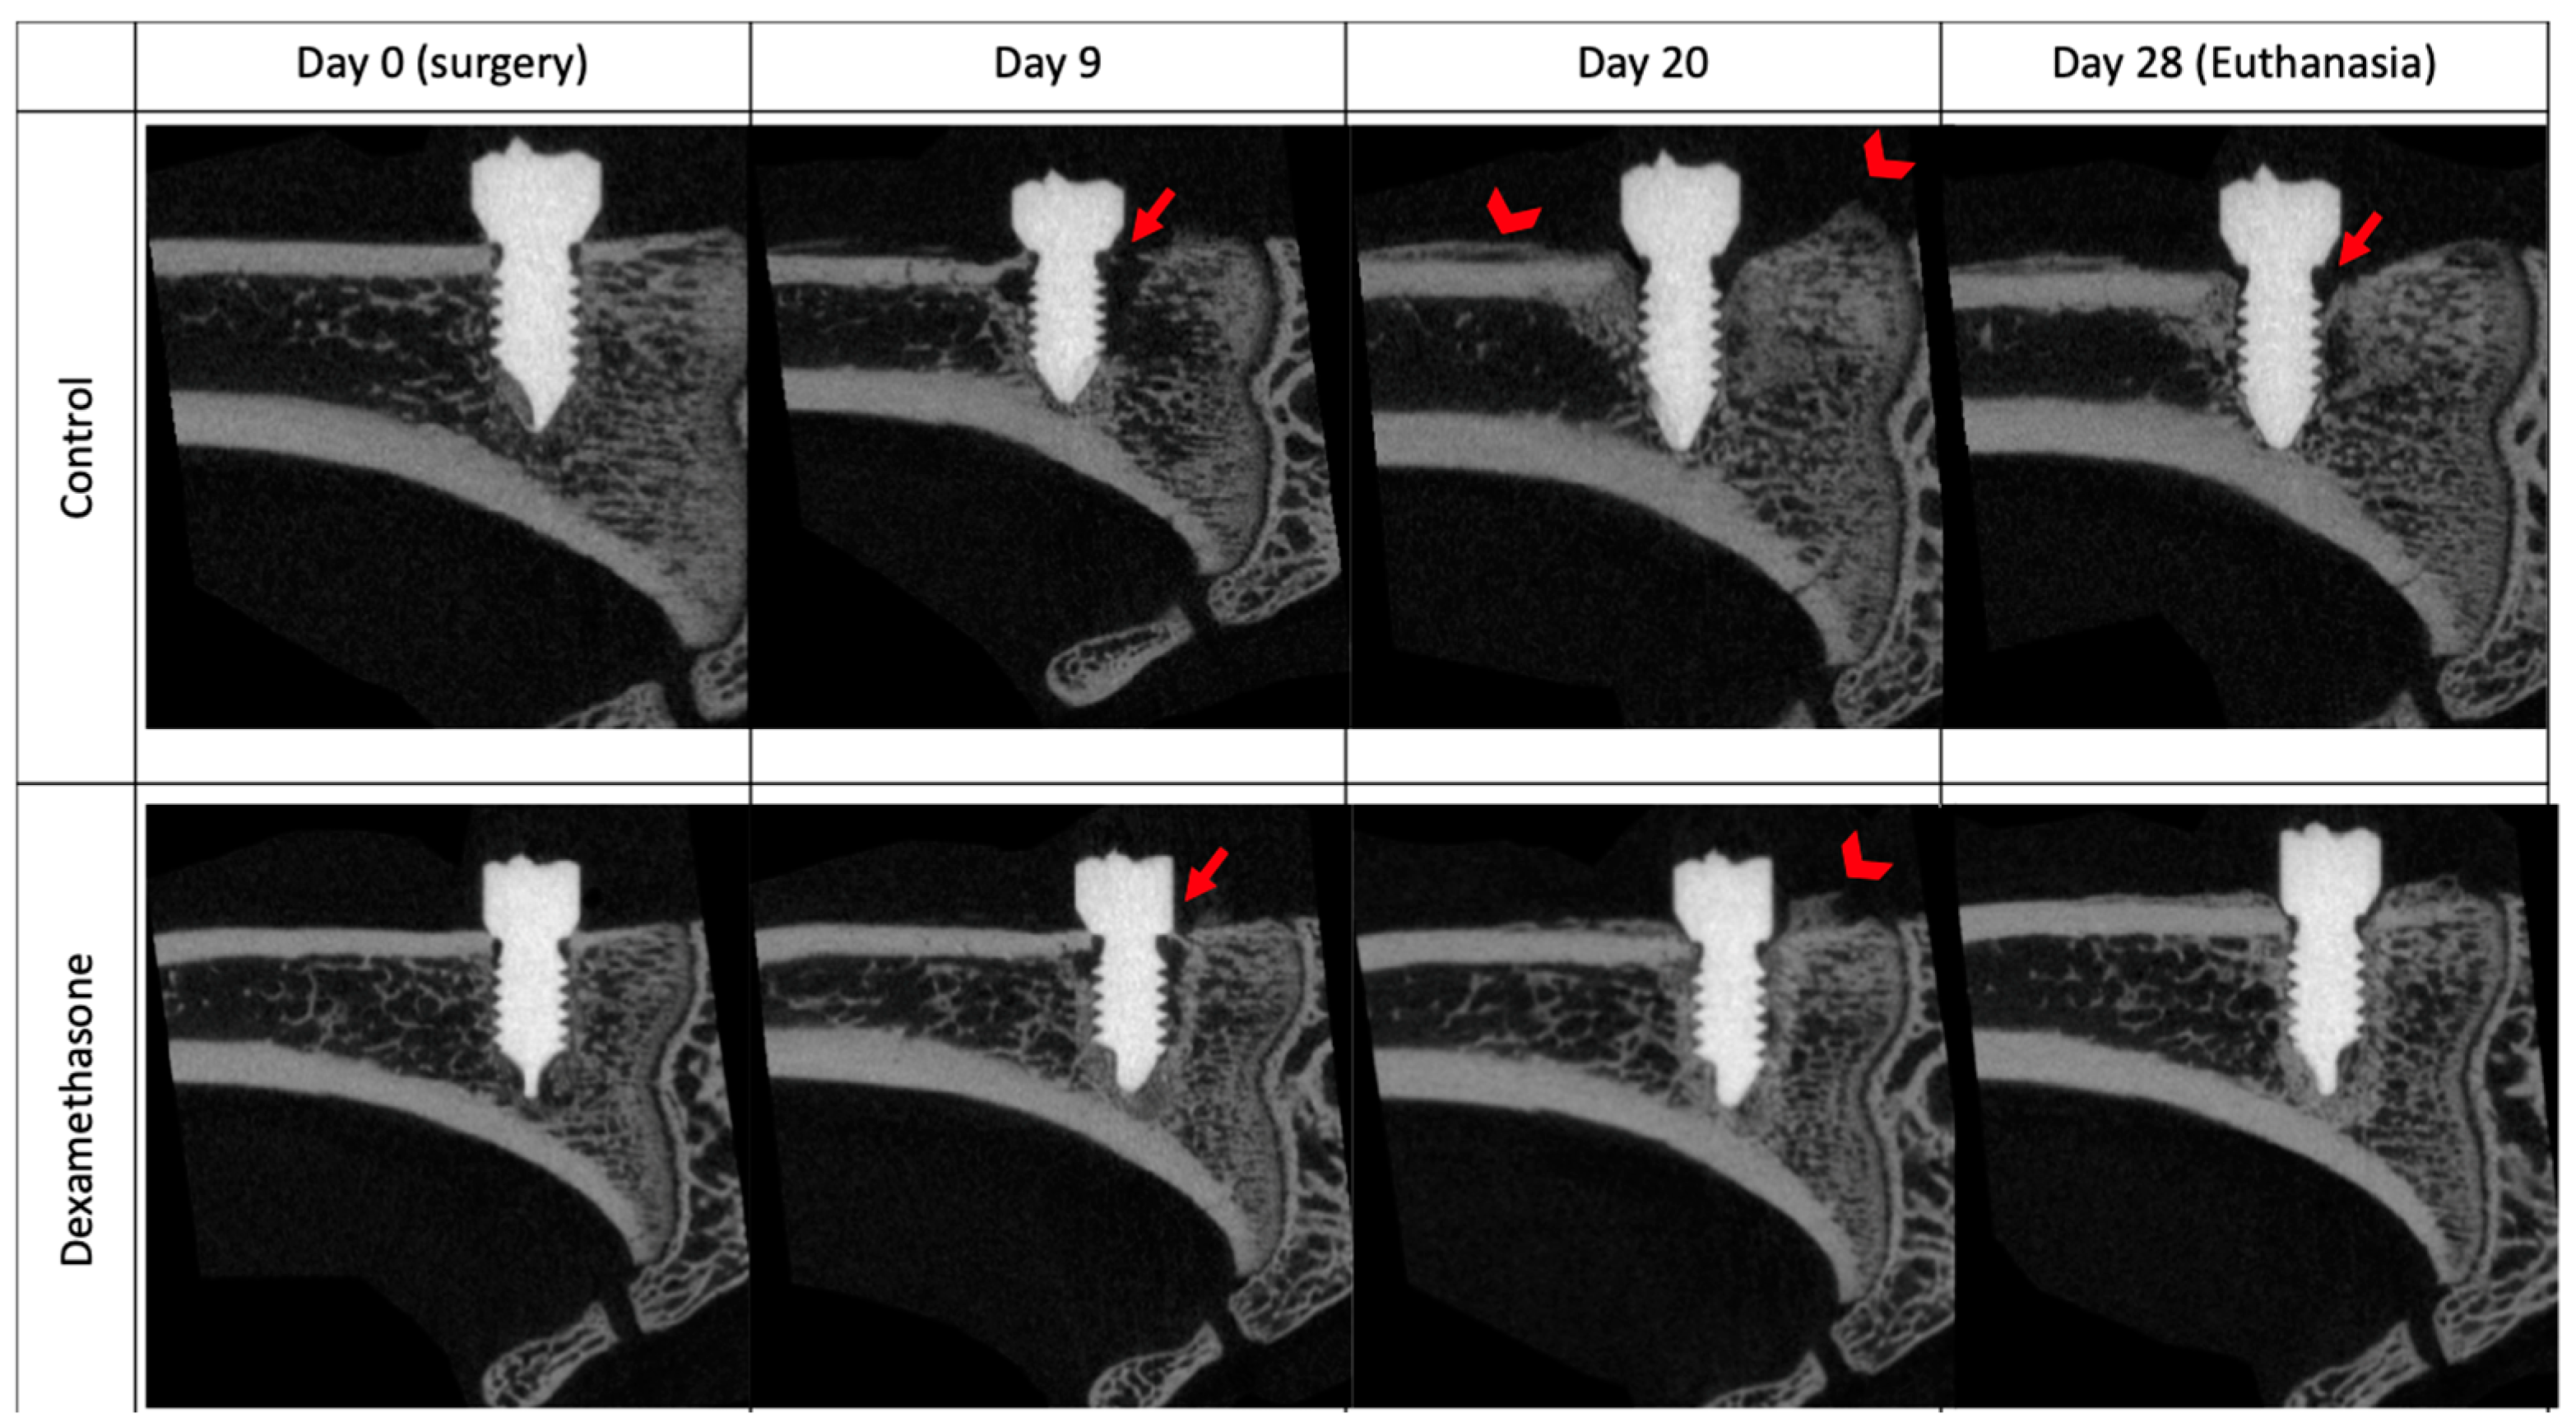

3.4. Cancellous Bone Changes in Response to Antibiotic Therapy and Continuous Dexamethasone Therapy

In the interference study, we evaluated the impact of a combined treatment comprising dexamethasone and antibiotics on the bone changes during S. epidermidis infection. The inclusion of dexamethasone did not result in a significant alteration in S. epidermidis-induced changes in BIC. However, we noted a statistically significant higher bone fraction (BV/TV) at day 20 and day 28 in the dexamethasone-treated group than in the control group. The magnitude of the difference is particularly marked during the phase in which the antibiotic treatment was administered and seems to remain stable once the antibiotic is discontinued. (Figure 4 and Figure 5).

Figure 5. Illustrative time series of in vivo microCT scans from the interference study. The upper line shows the scans of an animal from the control group. The lower line shows the scans of an animal treated with 0.3 mg/kg BW dexamethasone daily. The lines of images are each taken from the same animal. The depicted scans were chosen based on median BV/TV values from each experimental group. Arrows indicate regions of osteolysis, arrowheads show periosteal reaction.